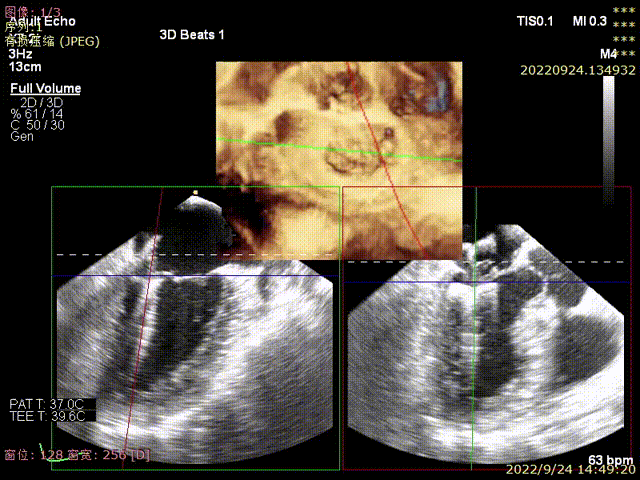

图3,由于患者反流位置位于3区偏交界,在MultiVue模式指导下进行操作

图4,夹子植入后消除P3区反流,残余P3偏P2区反流

图5-7,第二夹子植入后,反流降至轻微,术后平均跨瓣压差3mmHg